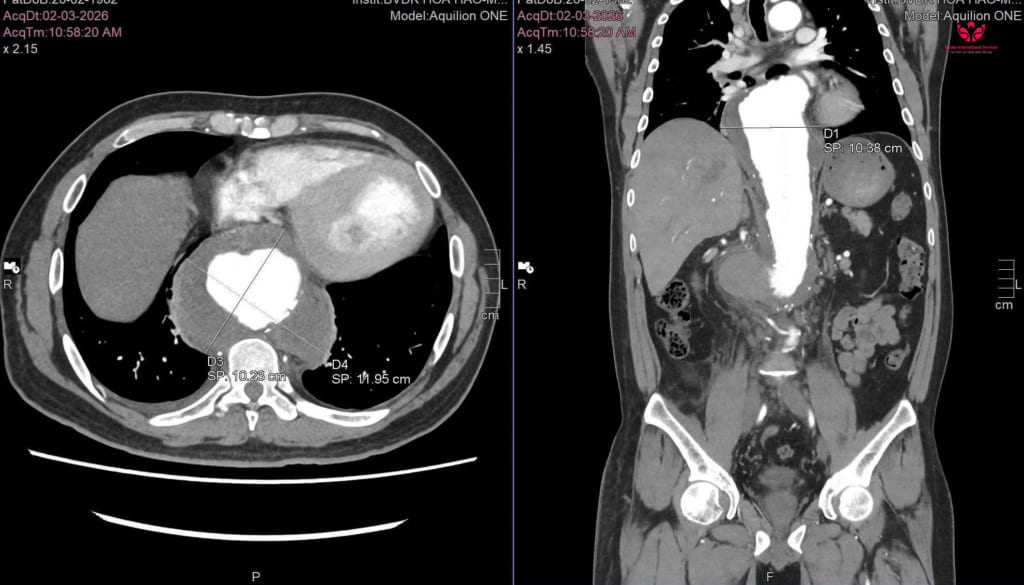

Anh L.Q.L (44 tuổi, ngụ tại Cần Thơ) nhập viện tại S.I.S Cần Thơ trong tình trạng đau bụng dữ dội. Qua kết quả khám và chụp CTA của bệnh viện tuyến trước, cho thấy anh L. đang trong tình trạng cấp cứu đe dọa tính mạng: phình động mạch chủ ngực – bụng đã vỡ kèm khối máu tụ lớn sau phúc mạc, đường kính khổng lồ lên đến 11cm.

Hình ảnh CT cho thấy kích thước khối máu tụ